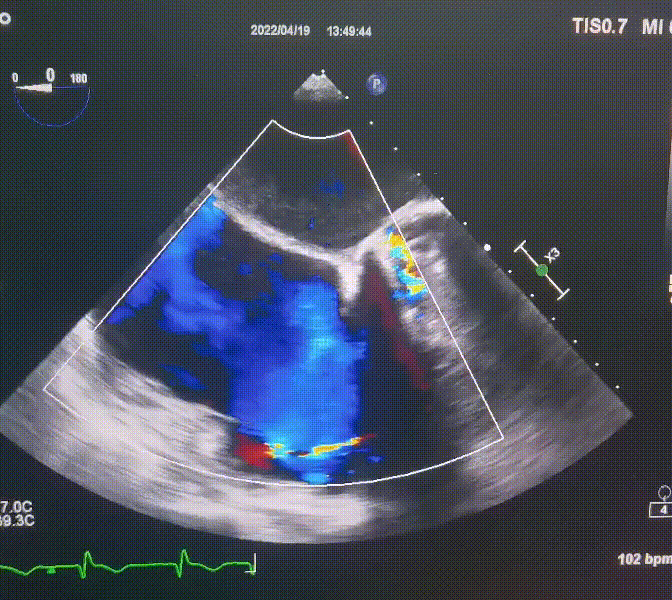

此次手術在全麻下進行,采用經(jīng)右側頸靜脈入路。術中在經(jīng)食道超聲和DSA的指引下多個維度精細調(diào)整輸送器角度,在達到正確位置后,逐步釋放瓣膜錨定裝置和盤片,最終完成瓣膜植入。術后患者右房壓明顯下降,術后超聲提示人工三尖瓣同軸性良好,瓣架固定牢靠,無反流和瓣周漏,血壓術后即刻上升20mmHg左右,手術后監(jiān)護室順利拔除氣管插管,3天后恢復良好,予以出院。

圖2.術后超聲